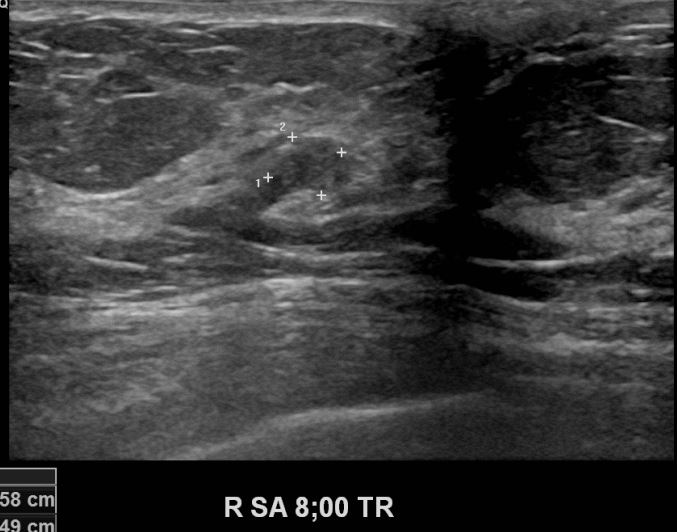

상기환자 건강검진상 이상소견으로 내원하신 60대 여성분으로 초음파검사이후

의심스러운 우측유방의 혹 조직검사 시행후 유방암 진단되었읍니다